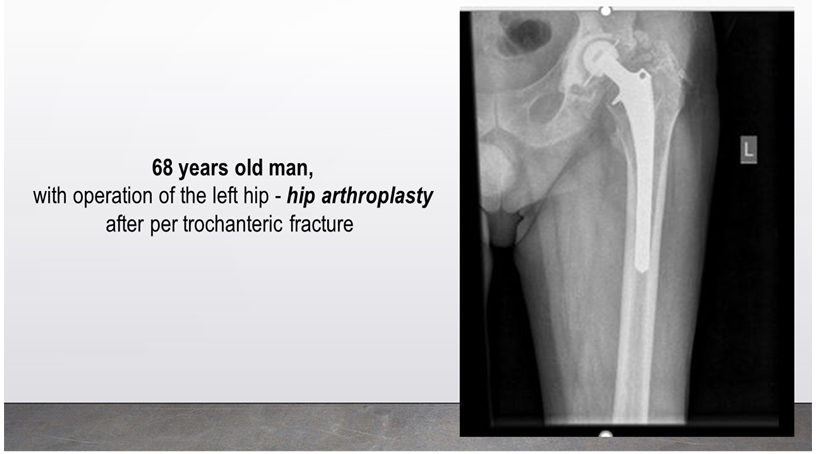

In geriatric rehabilitation, major goals are the improvement of the range of motion (ROM) of the hip, verticalization of the patient and gait training with gradual Weight-Bearing (WB – from 0% to 100%). Next figures (Figures 6–12) present data of some of our in-patients (X-ray) at the admission in the orthopaedic department (Figure 6) and / or in our PRM-Department (Figures 7–12). We proceed the rehabilitation of different type of patients: with Intertrochanteric fractures and subsequent hip replacement (Figure 6,7), with metallic osteosynthesis of the femoral body after a peri-prosthetic fracture (previous hip replacement) (Figure 8), with hip re-arthroplasty after a periprostheticdiaphyseal femoral fracture (Figure 9), with inter-trochanteric fracture and subsequent orthopedic surgery – intramedullary nailing (Figure 10), with per-trochanteric fracture, operated with implantation of metallic osteosynthesis – PCOM with DHS plaque (Figure 11), with proximal diaphyseal femoral fracture with dislocation and intervention of PCOM with DHS plaque (Figure 12).

Figure 7 Hip replacement after per-trochanteric fracture.